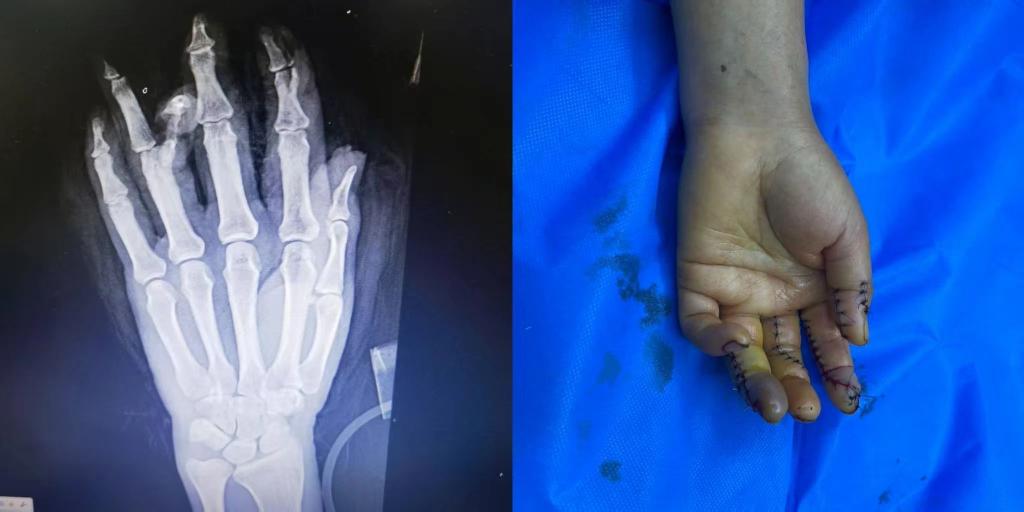

5月1日下午15点30分,beat365中文官方网站第五临床医学院2020级临床医学班的学生小马(化名)接到了来自伊犁亲戚的电话。电话中得知,亲戚在工作中不幸遭遇意外,左手被机器压伤,导致拇指、食指、中指、无名指均受到不同程度的损伤,受伤最严重的是食指和无名指,竖向劈开了骨头。由于多指多段离断的严重毁损伤,手术难度很大,当地医院的条件有限,为保住患者手指,需要申请前往上级医疗机构治疗。

随后,患者被送入手术室,由李华医生主刀,进行了长达7个小时的断指再植手术。

术后患者损伤严重的手恢复了基本形态,手指末梢血液循环逐步恢复。目前患者的情况基本平稳,在医院等待进一步观察和恢复。